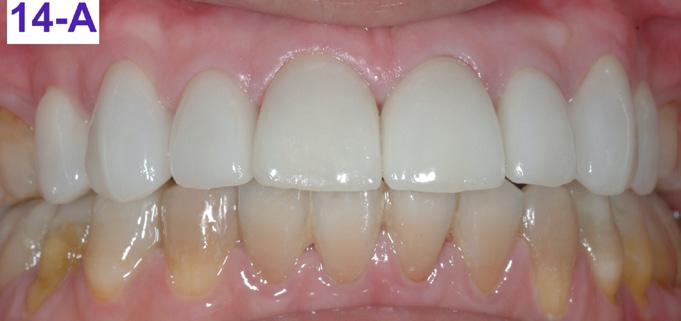

Six months after the de-bracketing, the patient requested replacement of his eight deteriorating porcelain veneers in the maxillary arch (Figure 14 – A).

FIG. 14A: Bonded porcelain veneers, frontal view